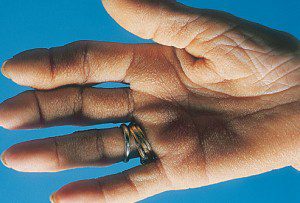

بیماری (Tripe Palms)

گاهی پوست کف دست ضخیم و به رنگ سفید مخملی شده و چین های آن تشدید می گردد و به عبارتی پوست شبیه سیرابی پخته گوسفند می شود. حدود 90 % موارد می تواند با سرطان ها مرتبط باشد. اگر فقط کف دست درگیر است به احتمال زیاد سرطان ریه وجود دارد ولی اگر هم زمان آکانتوزیس نیگری کانس نیز وجود داشته باشد معمولاً به دلیل سرطان دستگاه گوارش می باشد.